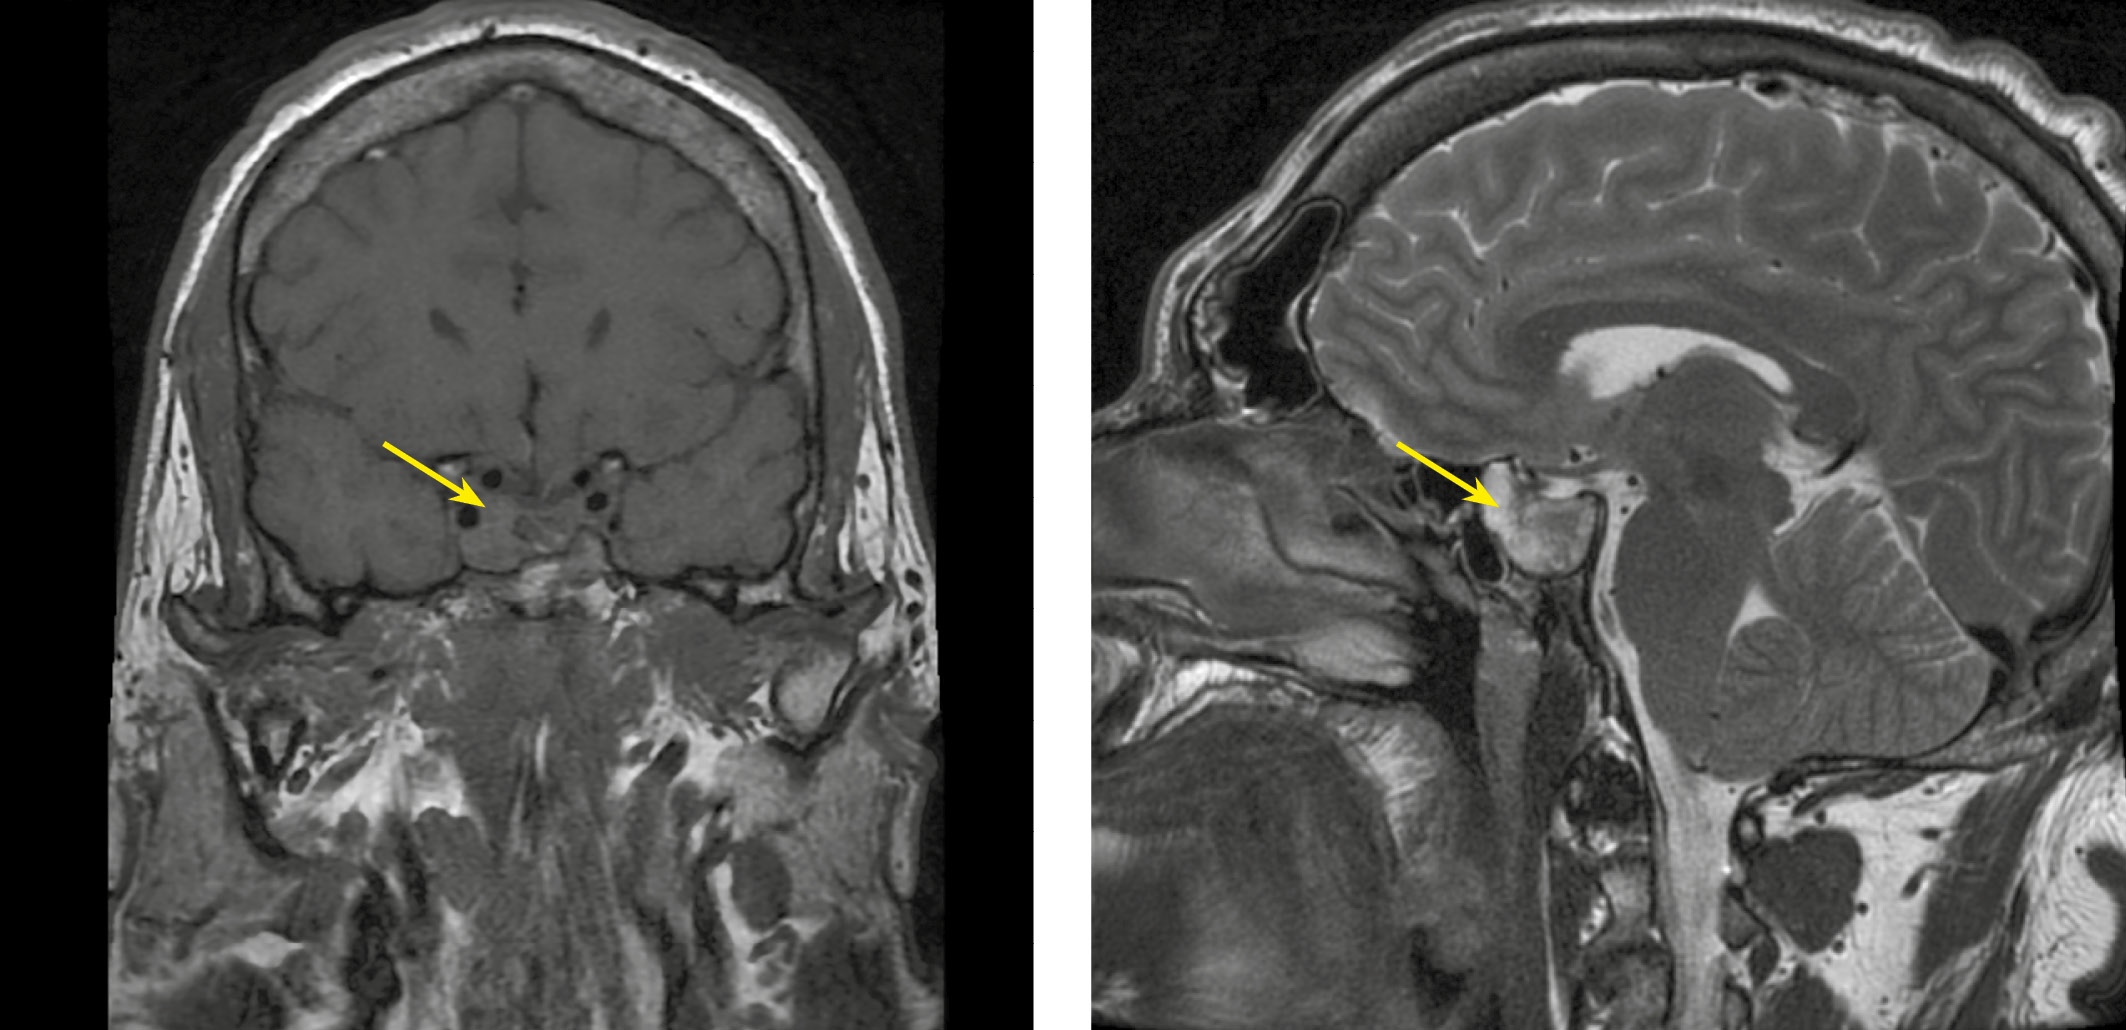

Во время госпитализации подтверждена активная стадия акромегалии: выявлено повышение уровня ИФР-1 до 1341 нг/мл (82–283), по результатам магнитно-резонансной томографии (МРТ) головного мозга визуализирована макроаденома гипофиза размерами 36×33×26 мм (рис. 1). Консультирован нейрохирургом, рекомендовано оперативное лечение.

Рисунок 1. МРТ головного мозга пациента Д. с внутривенным контрастированием:

в полости турецкого седла, в супраселлярной цистерне, в области дна третьего желудочка, в правом кавернозном синусе, в пазухах основной кости имеется многоузловое объемное образование неоднородной структуры размерами: вертикальный — 36 мм, поперечный — 33 мм, переднезадний — 26 мм, образование деформирует, смещает и компримирует хиазму, деформирует медиальную стенку левого кавернозного синуса; при контрастном усилении характеризуется сниженным (по сравнению с тканью аденогипофиза) накоплением контрастного препарата.